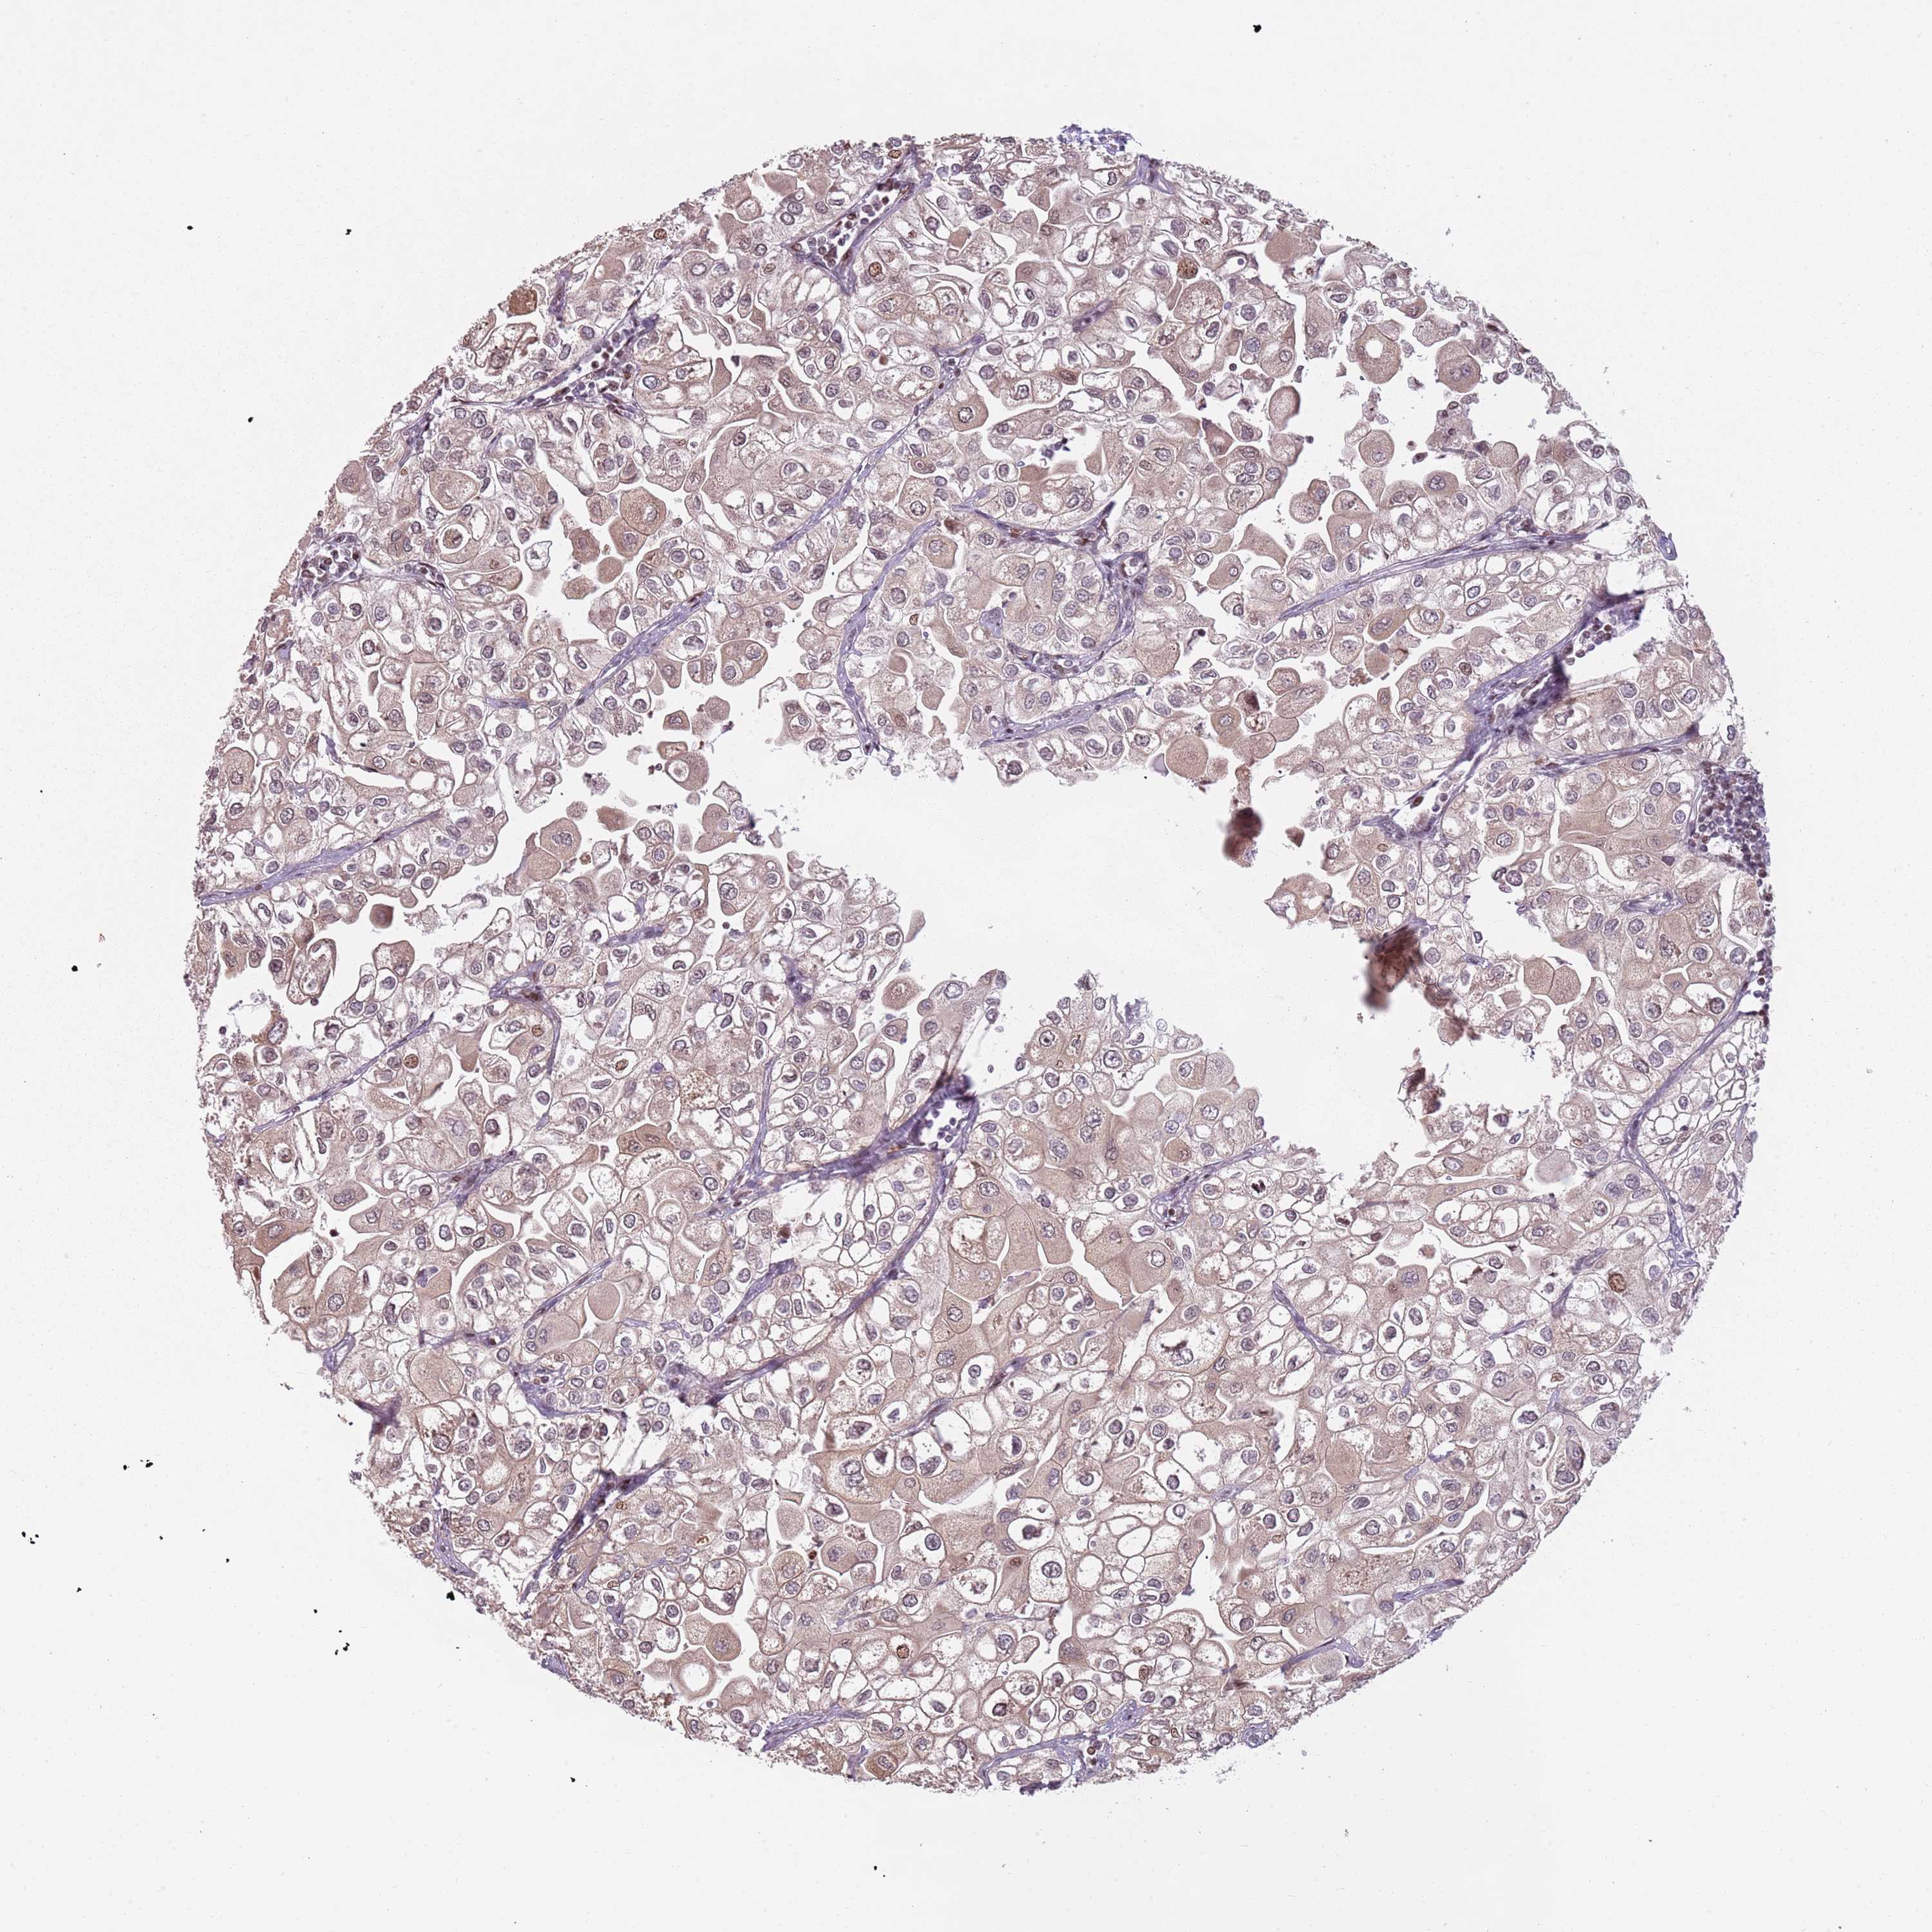

UROTHELIAL CANCER - Protein expressioni

A mouse-over function shows sample information and annotation data. Click on an image to view it in a full screen mode. Samples can be filtered based on level of antibody staining by selecting one or several of the following categories: high, medium, low and not detected. The assay and annotation is described here.

Note that samples used for immunohistochemistry by the Human Protein Atlas do not correspond to samples in the TCGA dataset.

Antibody stainingi

Antibody staining in the annotated cell types in the current human tissue is reported as not detected, low, medium, or high, based on conventional immunohistochemistry profiling in selected tissues. This score is based on the combination of the staining intensity and fraction of stained cells.

Each image is clickable and will lead to virtual microscopy that enables deeper exploration of all samples and also displays staining intensity scores, fraction scores and subcellular localization as well as patient and tissue information for each sample.

Antibody HPA046065

Staining

High

Medium

Low

Not detected

Intensity

Strong

Moderate

Weak

Negative

Quantity

>75%

75%-25%

<25%

None

Location

Nuclear

Cytoplasmic/membranous

Cytoplasmic/membranous,nuclear

Urothelial carcinoma, High grade

Urothelial carcinoma, Low grade